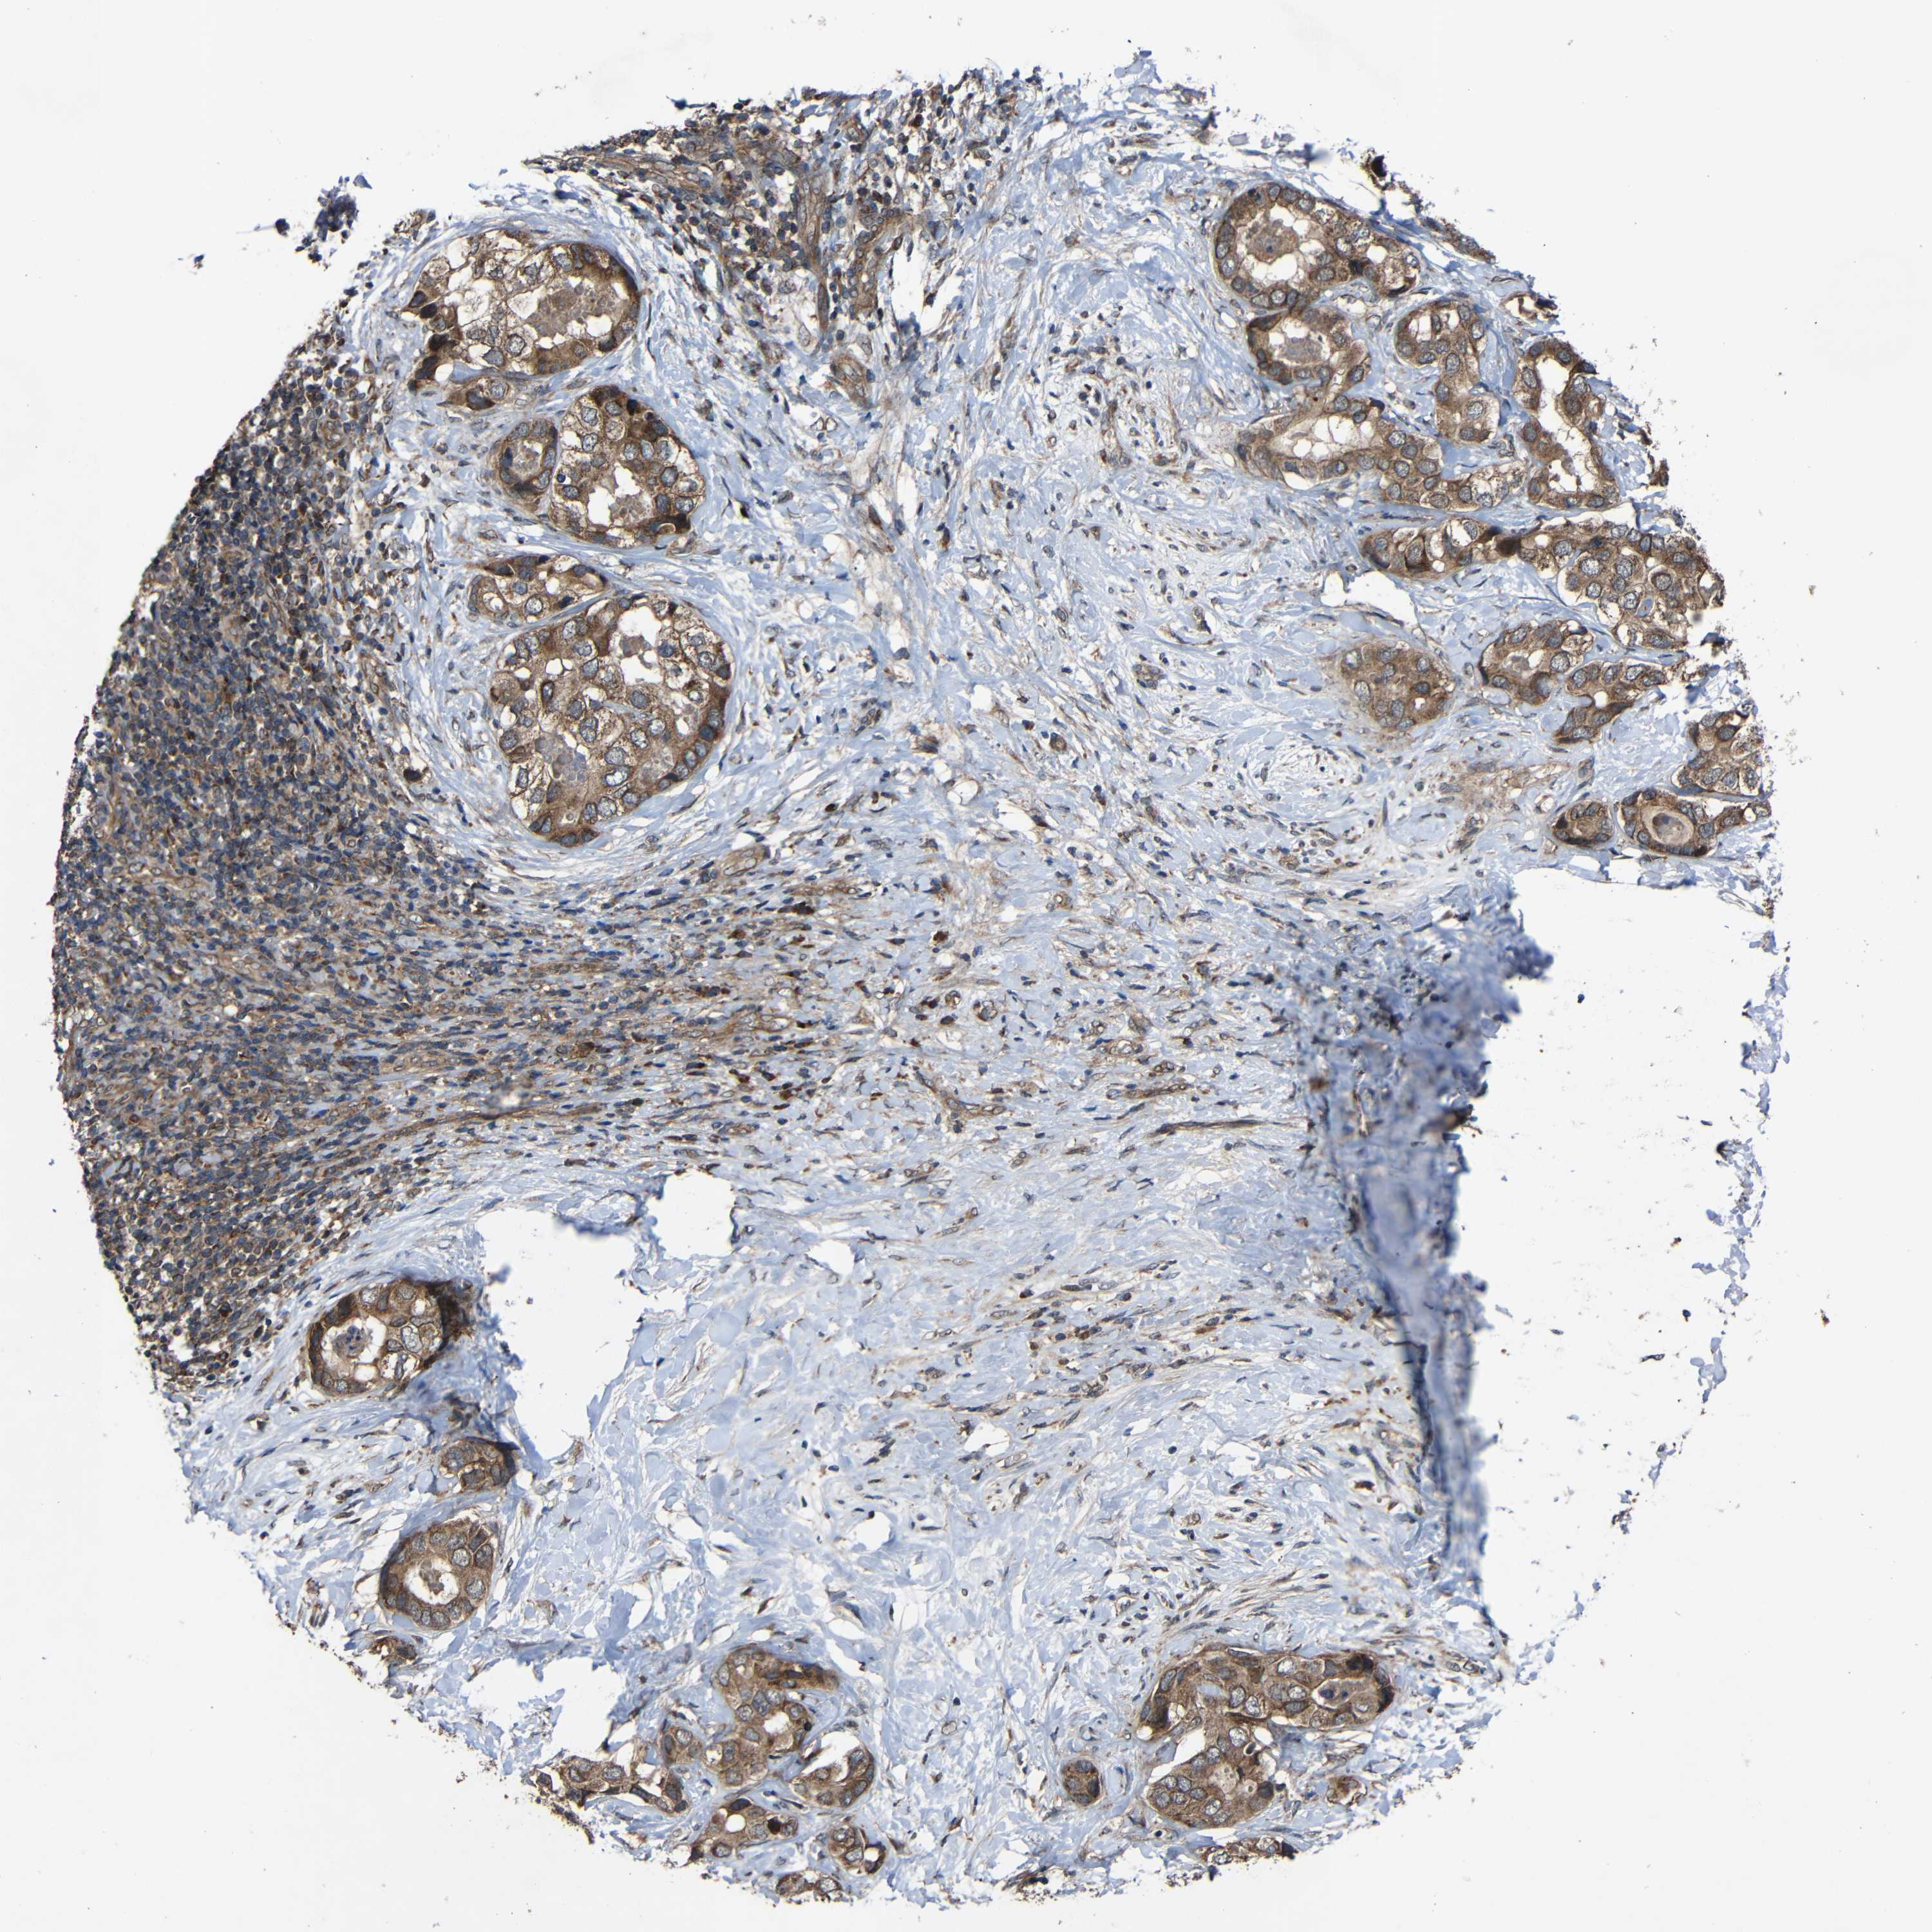

LIVER CANCER - Protein expressioni

A mouse-over function shows sample information and annotation data. Click on an image to view it in a full screen mode. Samples can be filtered based on level of antibody staining by selecting one or several of the following categories: high, medium, low and not detected. The assay and annotation is described here.

Note that samples used for immunohistochemistry by the Human Protein Atlas do not correspond to samples in the TCGA dataset.

Antibody stainingi

Antibody staining in the annotated cell types in the current human tissue is reported as not detected, low, medium, or high, based on conventional immunohistochemistry profiling in selected tissues. This score is based on the combination of the staining intensity and fraction of stained cells.

Each image is clickable and will lead to virtual microscopy that enables deeper exploration of all samples and also displays staining intensity scores, fraction scores and subcellular localization as well as patient and tissue information for each sample.

Antibody HPA011294

Antibody HPA012819

Staining

High

Medium

Low

Not detected

Intensity

Strong

Moderate

Weak

Negative

Quantity

>75%

75%-25%

<25%

None

Location

Nuclear

Cytoplasmic/membranous

Cytoplasmic/membranous,nuclear

Cholangiocarcinoma

Carcinoma, Hepatocellular, NOS